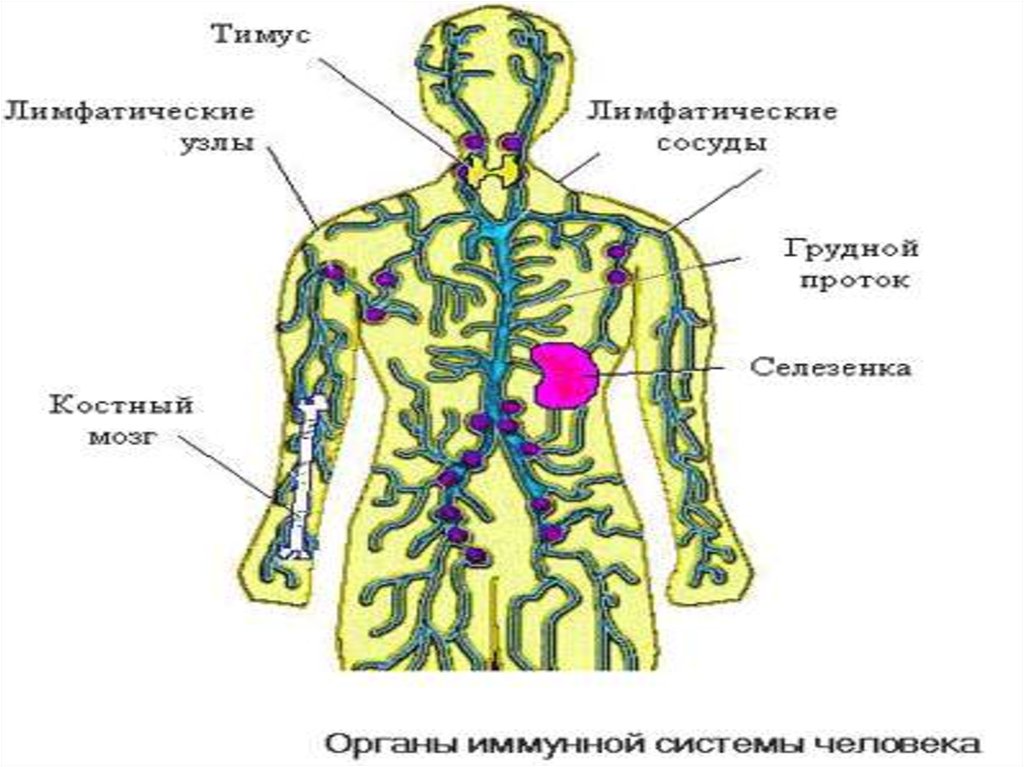

Изображения и схемы: как выглядит лимфа